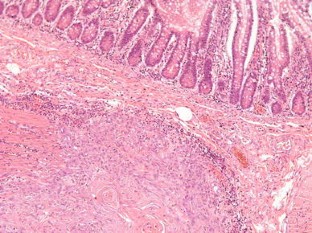

In both patients, the degeneration of mesh infection into SCC was presumably caused by the long-term inflammation secondary to infection. Patients presented with advanced SCC behaving just like the Marjolin’s ulcers of burns. Radical surgical excision was the treatment of choice. The involvement of the bowel played an additional challenge in case 1, but it was possible to resect the tumor and the involved bowel and reconstruct the abdominal wall using polypropylene mesh as onlay reinforcement, in a single stage operation. He is now under adjuvant chemotherapy. The big gap in the midline after tumor resection in case 2 required mesh bridging to close the defect. The poor prognosis of case 2 who died months after the operation, and the involvement of the armpit, groin and mesenteric nodes in case 1 shows how aggressive this disease can be.

Fig. 7

Fig. 8